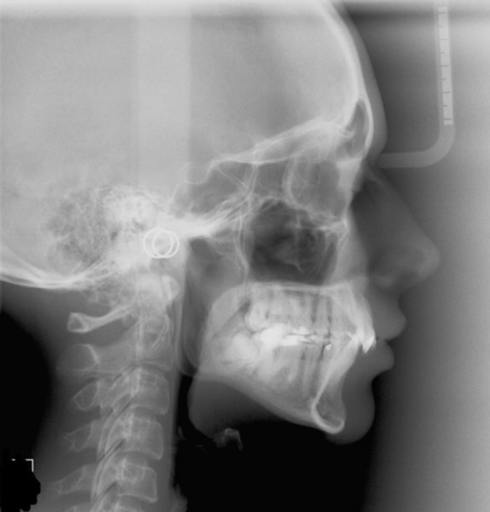

I need open bite sugery. i have had braces 2 times. The first time I finished it 18 months, then moved. My insurance changed so they said i would have to get a new referal to a oral surgon. So i went to the dentist and he said i should go to the orthodotist first and he knew a really good guy that was across the hall. The orthodontist said i would need braces again to align my teeth and close reopen bite before the surgery and would need a full round of braces and it would be 2500 after insurance. I was very surprised because my teeth looked very straight to me, but my mom said since the ortodontist said it i have to get braces again. so after i finished this my teeth looked exactly the same and i couldnt offers to do the sugery. now fast foward a few years. Im 21 now still on my moms insurance and i went to a new orthodontist to get a referral to a oral surgeon and The orthodontis said he didnt think braces could close my bite but I should get them any way to help align my teeth.

In this image of my condyles, do they appear normal/healthy or is there any bone loss?

Attached is an image of my condyles. Are they normal and healthy or Do you see any bone loss such as flattening or erosion of them? If there does appear to be some bone loss, how does this affect my bite and the appearance/position of my jaw?? Is...